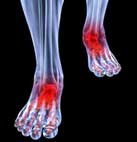

9. Đau khớp ngón chân: Nếu đang phải chịu đựng những cơn đau xuất hiện đột ngột kèm theo triệu chứng sưng và cứng khớp cùng lúc ở hai ngón chân cái hoặc 2 ngón tay trỏ, bạn nên nghĩ đến bệnh viêm khớp dạng thấp (RA). Đây là một dạng thoái hóa khớp, với những biểu hiện đầu tiên thường xuất hiện trên các khớp nhỏ như ở ngón chân và ngón tay. Phụ nữ có nguy cơ cao gấp 4 lần so với nam giới.

Giải pháp: Sau khi gặp bác sĩ chuyên về khớp để xác định nguyên nhân, bạn có thể được chữa trị bằng thuốc hoặc các liệu pháp giúp giảm đau và bảo toàn chức năng của khớp. Việc chẩn đoán sớm rất quan trọng, giúp bệnh nhân tránh tình trạng bị biến dạng vĩnh viễn cấu trúc bàn chân hoặc ngón chân.